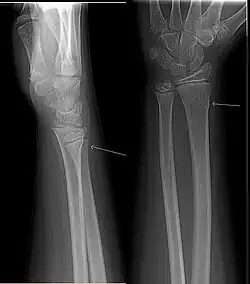

Złamanie zielonej gałązki

Złamanie „zielonej gałązki”, złamanie podokostnowe (ang. greenstick fracture) – złamanie częściowe kości charakterystyczne dla wieku dziecięcego, w którym albo nie dochodzi do przerwania relatywnie grubej w tym wieku okostnej (złamanie podokostnowe, częste u najmłodszych dzieci) albo dochodzi do niego tylko z jednej strony (typowe „złamanie zielonej gałązki”). Nazwa zaczerpnięta została ze sposobu niecałkowitego przerwania kości przypominającego dosłownie złamanie młodej, giętkiej gałązki krzewu. Znamienny dla tego typu urazów jest brak przemieszczenia odłamów albo jego niewielki stopień, a to z powodu „szynującej” roli silnej okostnej.

W obrazie rentgenowskim charakterystyczny jest brak szczeliny złamania (albo jest ona słabo widoczna), okostna jest odwarstwiona przez krwiak.